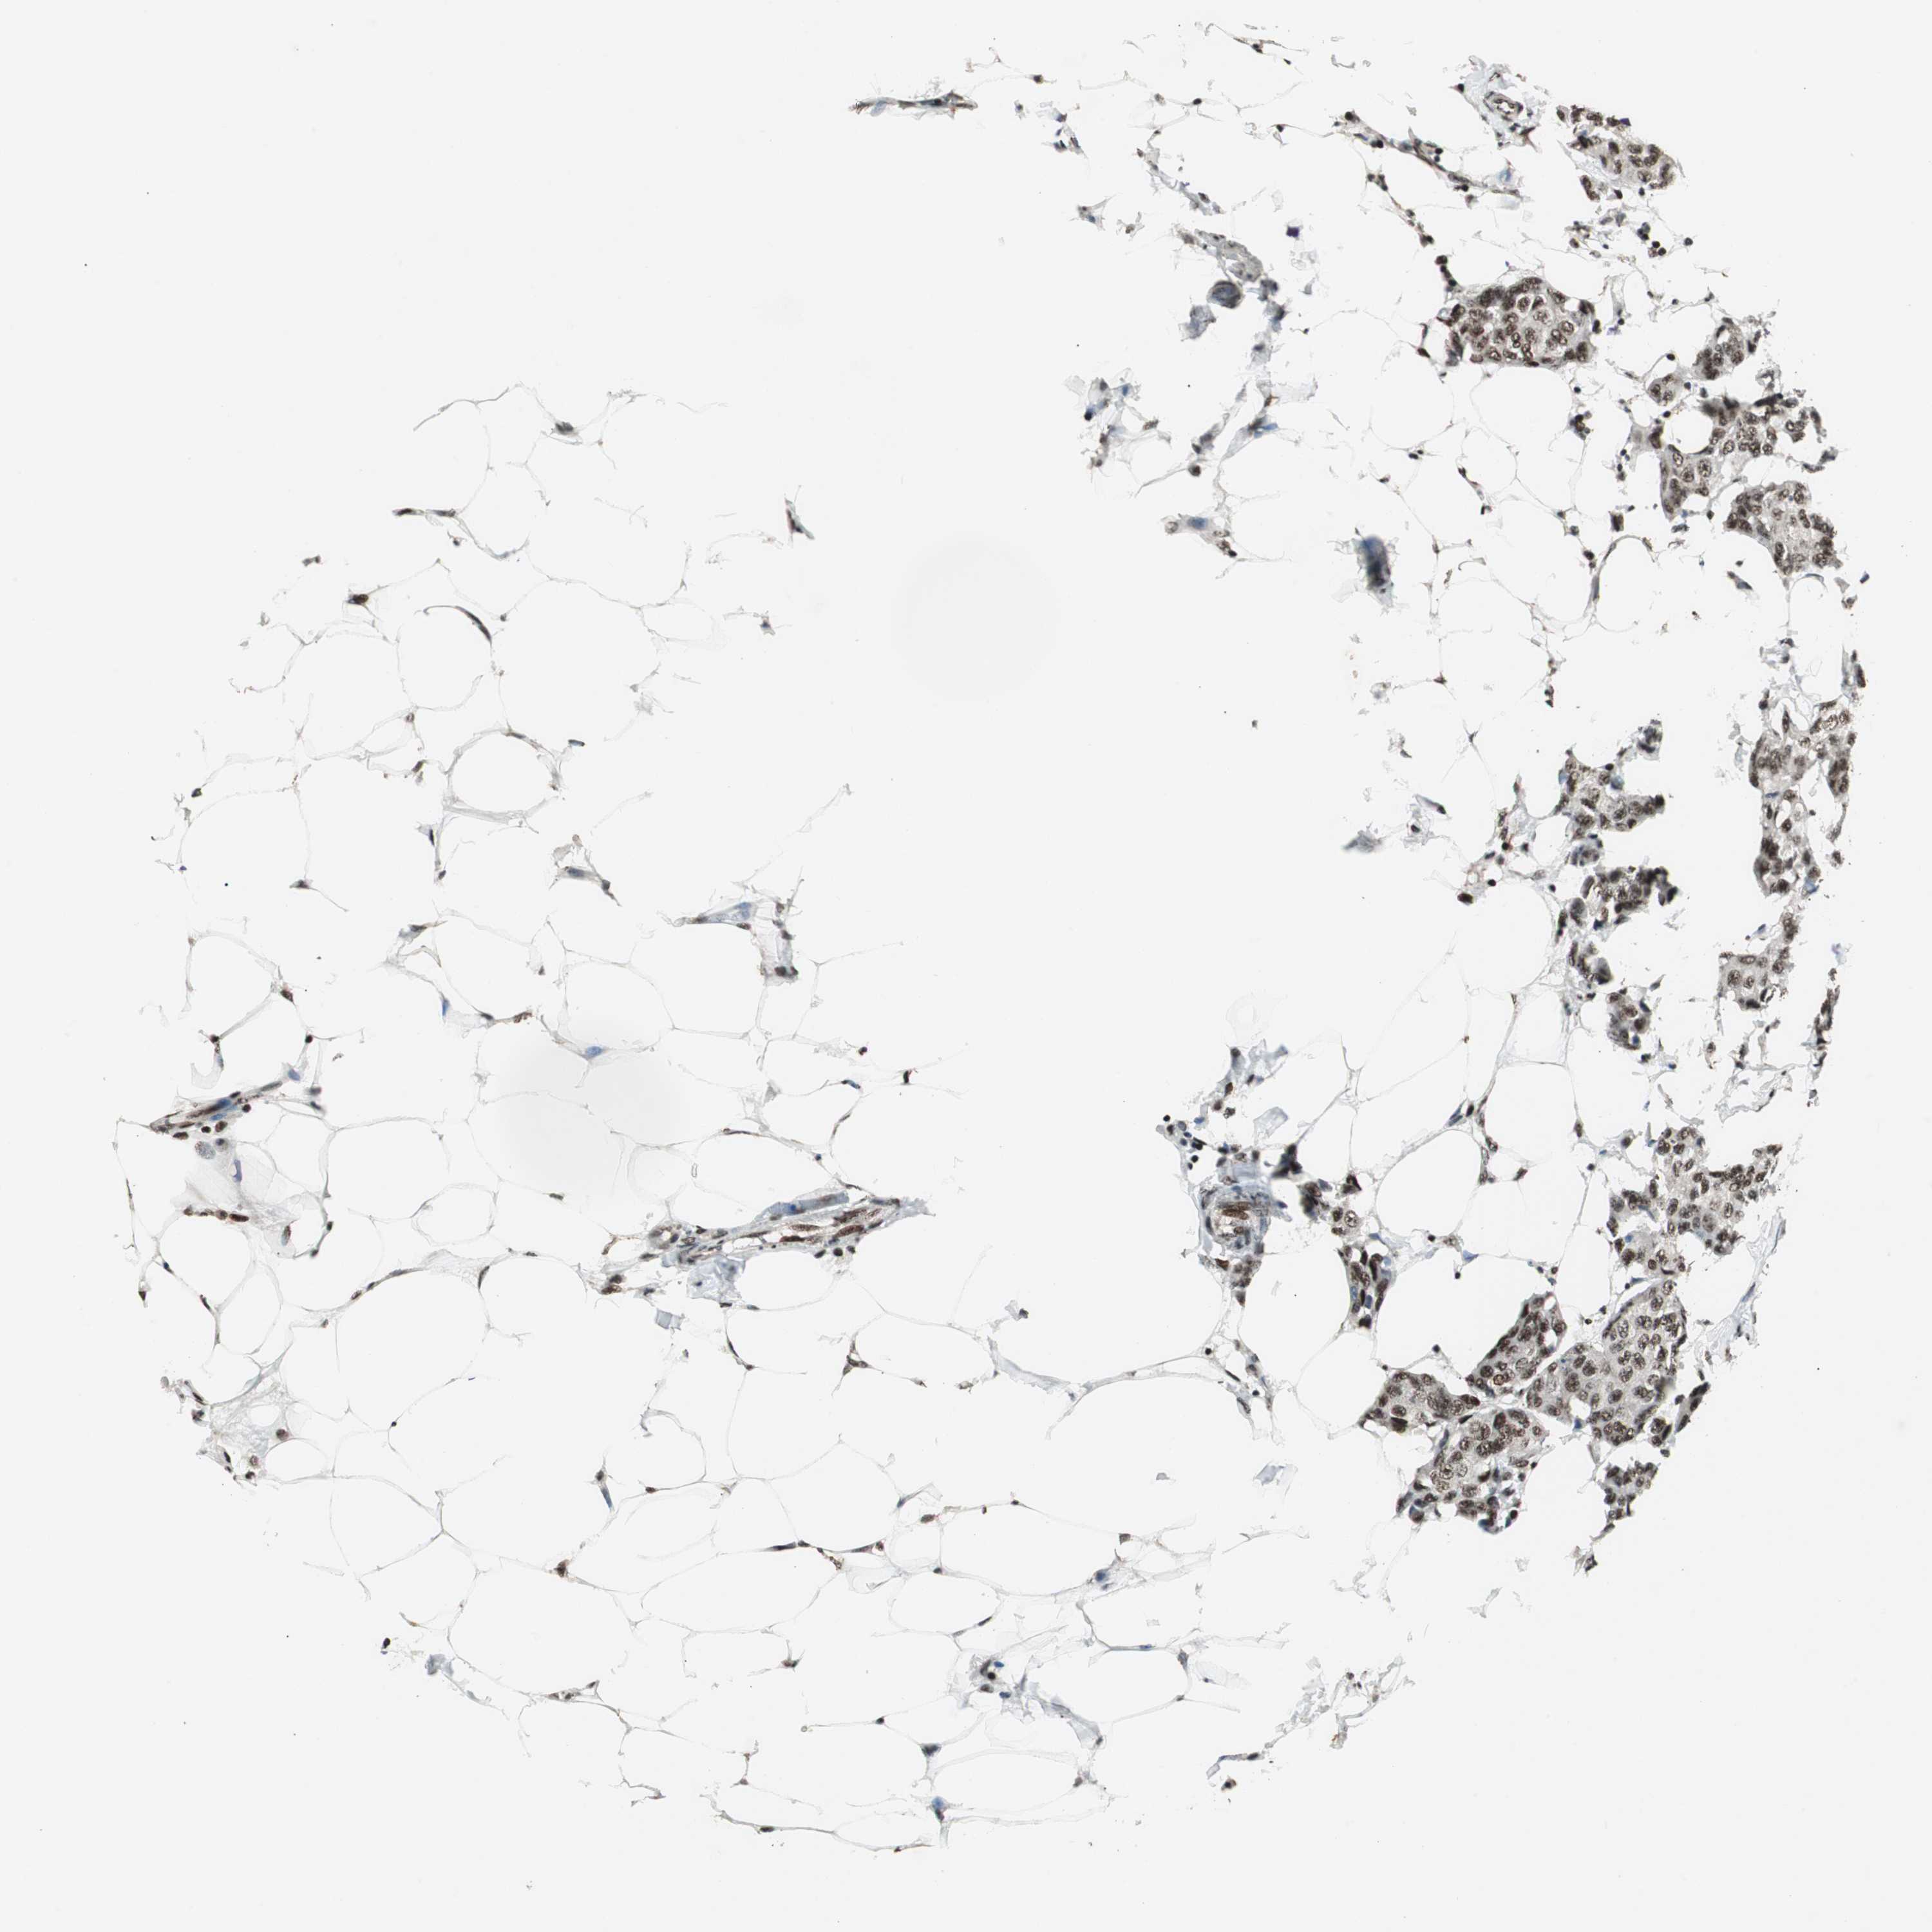

BRCA TCGA BRCA VALIDATION PROTEIN EXPRESSION